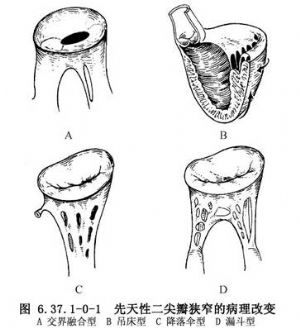

①交界融合型:瓣叶交界处融合导致瓣口狭窄,瓣叶本身正常。瓣下乳头肌直接与瓣叶连接,可无腱索或腱索缩短,此型除瓣膜狭窄外,瓣下粗大的乳头肌也形成阻塞(图6.37.1-0-1A)。

②吊床型:主要病理改变为缺少两个正常的乳头肌,而是多个乳头肌或肌性纤维条束附着在左心室的后壁上方。二尖瓣前叶腱索跨过开口与后方的乳头肌相连,形似吊床。瓣膜组织一般正常且有弹性,与其他类型二尖瓣狭窄相比较,此型瓣膜没有一个中央开口,而是一个弧形的多个开口(图6.37.1-0-1B)。严重的病例,吊床型二尖瓣仅是一个有散在孔的纤维隔膜。血液经这些孔从左心房进入左心室。此型狭窄除瓣口窄小外,主要在瓣下乳头肌阻塞,可同时有关闭不全。

③降落伞型:瓣膜本身狭窄不重,而主要在瓣下阻塞,此型狭窄是二尖瓣狭窄最常见的病变。腱索由过多的瓣膜组织连接形成筛孔状隔膜附着于单一乳头肌或融合的两个乳头肌上(图6.37.1-0-1C)。在一些病例交界下裂口是血液从左心房进入左心室的惟一开口。

④漏斗型:此型与交界融合型不同之处在于瓣膜明显增厚和重度向下牵拉,有融合的腱索和正常乳头肌(图6.37.1-0-1D)。有些病例,由于瓣膜组织过多,连接前后叶形成二尖瓣的附加瓣口(二尖瓣双瓣口)。附加瓣口本身通常并不狭窄。